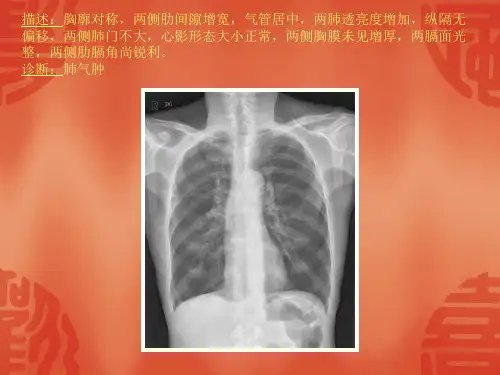

常见40张X片读片及诊断 ppt课件